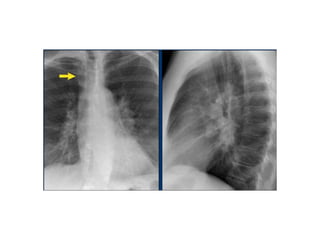

• In this case on the PA-view there is hilar enlargement.

On the PA-view it is not clear whether this is due to dilated

vessels or enlarged lymph nodes.

On the lateral view there are round structures in areas

where you don't expect any vessels. So we can conclude

that we are dealing with enlarged lymph nodes.

• This patient has sarcoidosis.

Notice also the widening of the paratracheal line (or stripe)

as a result of enlarged lymph nodes.

• In this case there is an enlarged hilar shadow on

both sides.

This could be the result of enlarged vessels or

enlarged lymph nodes.

A very helpful finding in this case is the mass on

the right of the trachea.

• This is known as the 1-2-3 sign in sarcoidosis, i.e.

enlargement of left hilum, right hilum and

paratracheal.